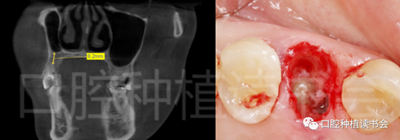

術(shù)前CBCT(美亞光電)檢查:47根分叉下方骨高度及骨寬度滿足即刻種植要求(圖13)。

圖13 47根分叉區(qū)骨寬度及骨高度(與下頜神經(jīng)管之間的距離)滿足即刻種植要求。

5.3.6 術(shù)后即刻CBCT(美亞光電)檢查種植體軸向及深度良好(圖19)。

圖19 術(shù)后即刻CBCT確認(rèn)種植體頰、

舌側(cè)骨板完整,并保持了足夠的厚度。